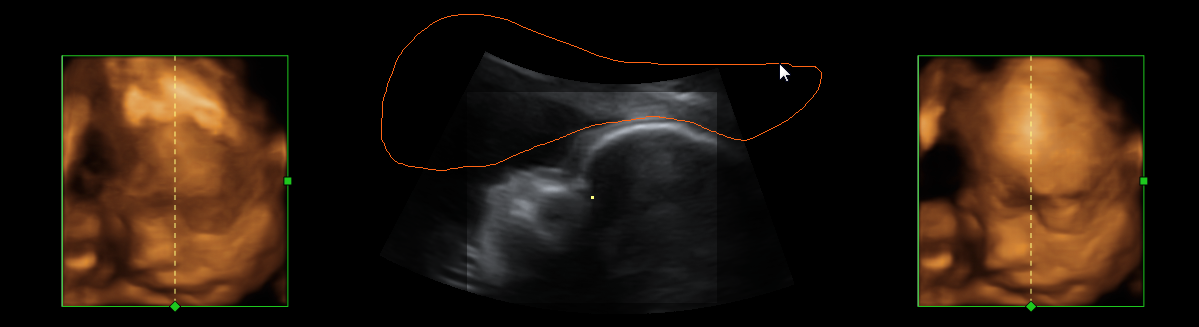

To increase robustness of the ultrasound segmentation, the various approaches are usually tailored for specific anatomies. Carneiro et al. have developed an automatic technique for segmenting the brain of a fetus carneiro08 . By first detecting the cerebellum, the system can narrow down the search for other features. On the other hand, segmentation is an extremely critical procedure which may obscure diagnostically relevant aspects of the anatomy under examination. Consequently, fully automatic segmentation techniques have not been implemented in clinical systems so far, with the exception of a method for follicle volumetry deutch09 , as shown in figure 3.

Refer to caption

Figure 3: Automatic segmentation of the ovarian follicles deutch09 .